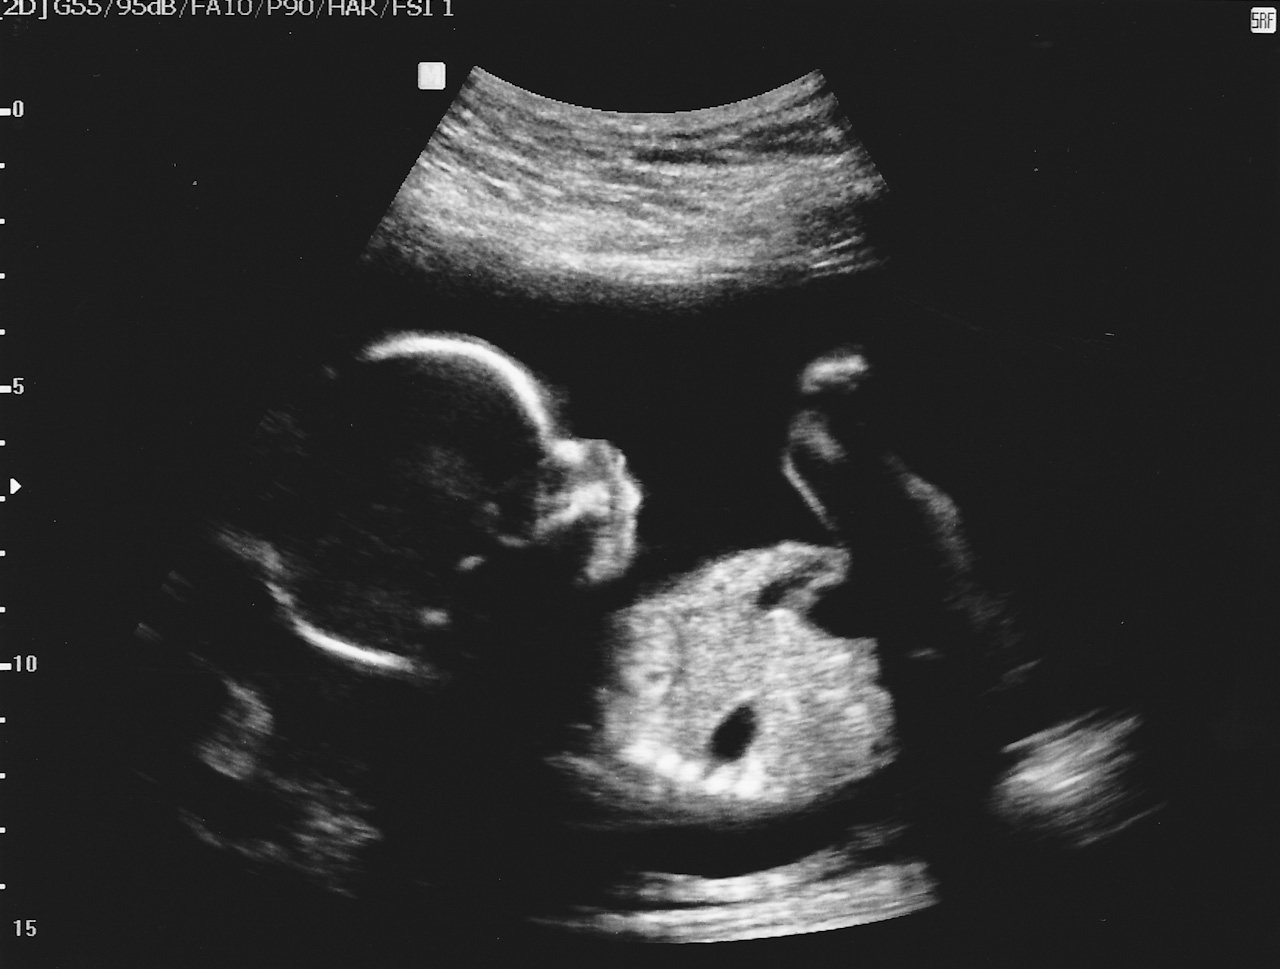

Categories events 20 Week Ultrasounds Post author By sean Post date October 10, 2012 More ultrasounds, at the half-way point. Starting to look more and more like a baby! Tags girl, ultrasounds